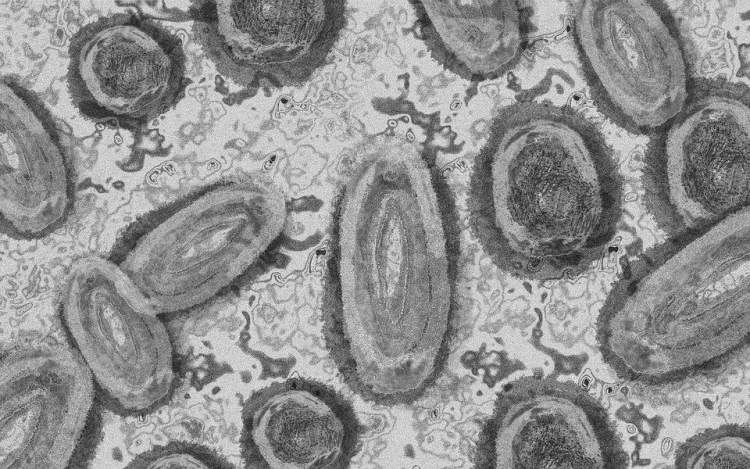

Újabb hét magyarnál igazolták a majomhimlőt

Újabb hét embernél igazolták a majomhimlőfertőzést a Nemzeti Népegészségügyi Központ (NNK) veszélyes kórokozókkal foglalkozó laboratóriumában; ezzel 19-re nőtt az igazolt majomhimlő fertőzöttek száma Magyarországon

- tájékoztatta az NNK csütörtökön az MTI-t.

Az NNK ismertetése szerint a vírus lappangási ideje általában 6-13 nap, de akár 5-21 nap is lehet. A betegség általános, nem specifikus tünetekkel, például lázzal, hidegrázással, izomfájdalommal, hátfájdalommal, fejfájással, fáradtsággal, a nyirokcsomók duzzanatával kezdődik, majd 1-3 nappal a bevezető tünetek után bőrkiütések jelennek meg.

A kiütések a legtöbb esetben először az arcon, majd leggyakrabban a tenyéren és a talpon fordulnak elő, de megjelenhetnek a szájnyálkahártyán, a nemi szerveken és a végbél környékén is - írták.